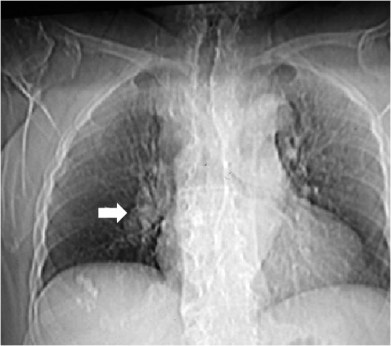

SIGNO DE FLEISHNER o DEL HILIO ABULTADO o DEL NUDILLO

En la radiografía posteroanterior o anteroposterior de tórax, la presencia de una arteria pulmonar agrandada puede indicar tromboembolismo, especialmente cuando no está presente en los estudios previos. Este signo también se llama signo de plump hilus o Signo del nudillo.

En el corte del angioTC de tórax con contraste del mismo paciente, vemos un aumento de tamaño de la arteria pulmonar, que presenta un defecto de repleción (flecha) correspondiente al tromboembolismo.